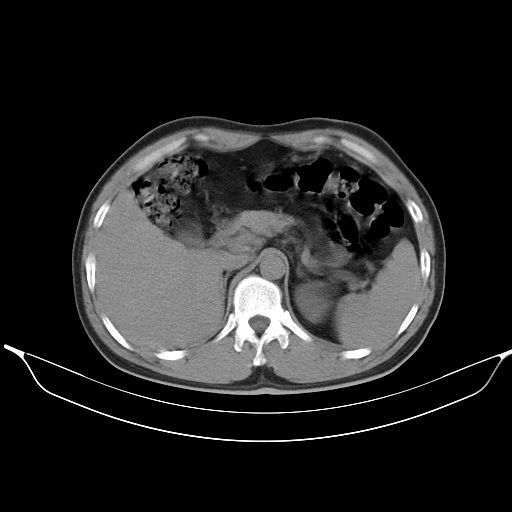

标题: CT25490:男,40岁,体检发现;无其它不适。 [打印本页]

标题: CT25490:男,40岁,体检发现;无其它不适。

考虑右下肺周围性肺癌并肺内多发转移,纵隔淋巴结转移!

支持 !考虑右下肺周围性肺癌并肺内多发转移,纵隔淋巴结转移,(气管前腔静脉后,隆突下,主动脉弓下都有了)

1、均为转移,原发灶不在肺内。2、肺癌肺转移。